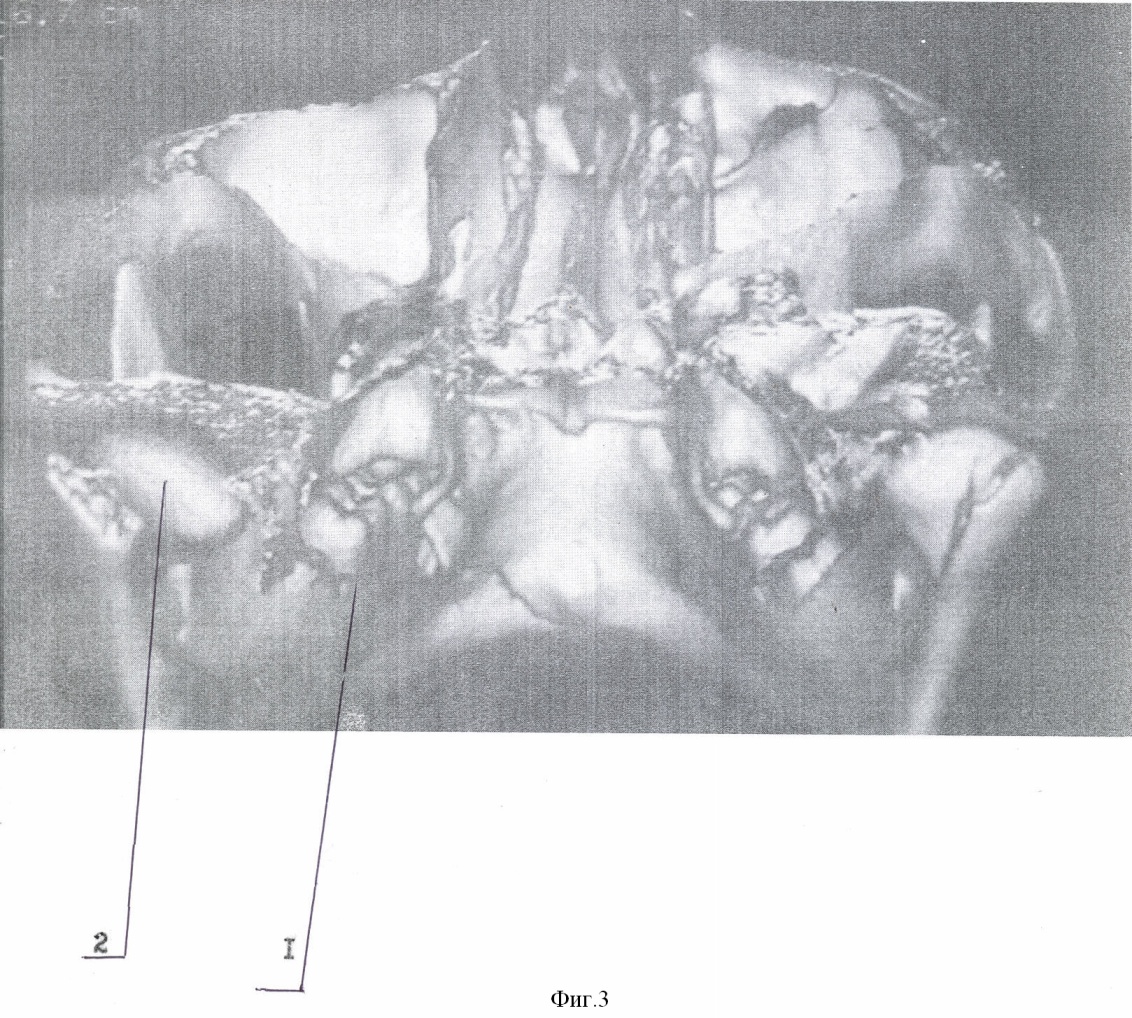

Способ осуществляют следующим образом. Типичным доступом через разрез кожи в подчелюстной области, окаймляющим угол нижней челюсти, осуществляют послойный доступ к линии перелома поднадкостнечно по латеральной поверхности ветви. Вывихнутый диссектором малый фрагмент вместе с суставной капсулой выводят в вырезку. Суставную капсулу рассекают вперед на 0,3-0,5 см. Отломок суставного отростка освобождают от суставной капсулы и выводят из раны. Фиброзные наложения раневых поверхностей костей удаляют. После оценки состояния отломка к участку, свободному от суставной поверхности, по заднему краю фиксируют микропластину (Т, Н, Х, L, Y-образной формы). Свободный конец микропастины изгибают для плотного прилегания к большему фрагменту по задней и латеральной поверхности ветви. Из суставной капсулы формируют ложе в суставной впадине. Малый фрагмент с подготовленной микропластиной устанавливают в ложе в анатомическом положении. Суставную капсулу над суставным бугорком укрепляют узловыми швами ПДС 4/0. Большой фрагмент репонируют на установленную в ложе конструкцию. Свободный конец микропластины фиксируют к заднелатеральной поверхности большего фрагмента микрошурупами. Осуществление способа и результат продемонстрированы на чертежах 1-8: фиг.1 – компьютерная томограмма (реконструкция) нижней челюсти, левая боковая; фиг.2 – компьютерная томограмма (реконструкция) нижней челюсти, вид сзади; фиг.3 – компьютерная томограмма (реконструкция) нижней челюсти, вид косо сзади; фиг.4 – собранная конструкция, вид сзади; фиг.5 – собранная конструкция, вид спереди; фиг.6 – компьютерная томограмма (реконструкция), вид спереди, после операции; фиг.7 – компьютерная томограмма (реконструкция) нижней челюсти, левая боковая, после операции; фиг.8 – компьютерная томограмма (реконструкция) нижней челюсти, левый суставной отросток, вид изнутри, после операции: где 1 – нижняя челюсть, 2 – отломок суставного отростка, 3 – титановая микропластина, 4 – микрошуруп, 5 – дренажная трубка.

Пример. Больной П., 14 лет поступил в отделение челюстно-лицевой хирургии ДККБ 20.04.07 г. с диагнозом: травматический тройной перелом нижней челюсти; перелом – вывих головки суставного отростка слева, перелом суставной головки справа без смещения, косой центральный перелом тела нижней челюсти со смещением (фиг. 1, 2, 3). 23.04.07 г. под общим обезболиванием выполнено оперативное вмешательство – открытая репозиция, металлоостеосинтез суставной головки слева Т-образной микропластиной, открытая репозиция, металлоостеосинтез косого перелома тела нижней челюсти двумя параллельными минипластинами. Типичным доступом через разрез кожи в подчелюстной области слева, окаймляющим угол нижней челюсти 1, осуществлен послойный доступ к линии перелома поднадкостнечно по латеральной поверхности ветви нижней челюсти. При помощи диссектора малый фрагмент мобилизован и вывихнут в вырезку вместе с суставной капсулой. Суставная капсула рассечена вперед на 0,5 см. Отломок суставного отростка 2 освобожден от суставной капсулы и выведен наружу. Фиброзные наложения на раневых поверхностях фрагментов удалены. По заднему краю отломка, по поверхности, свободной от суставной, при помощи микрошурупов 4 фиксирована Т-образная титановая микропластина 3, изогнутая для плотного прилегания к заднелатеральной поверхности большего фрагмента (фиг. 4, 5). Суставная капсула перемещена и расправлена в суставной ямке. В образованное ложе уложена конструкция в анатомическом положении. На края суставной капсулы над суставным бугорком наложены 2 узловых шва ПДС 4/0, обеспечивающие плотный охват отломка. Больший фрагмент репонирован на установленную конструкцию. Свободный конец микропластины 4 после небольшой коррекции изгиба фиксирован к заднелатеральной поверхности большего фрагмента микрошурупами 3. Рана послойно ушита с оставлением активного дренажа 5. Подчелюстным разрезом осуществлен послойный доступ к линии перелома тела нижней челюсти. Произведена типичная репозиция костных отломков, остеосинтез двумя параллельными минипластинами. Рана послойно ушита.

В послеоперационном периоде проводилась иммобилизация челюсти при помощи шин Васильева с межчелюстными вытяжениями. На контрольно компьютерной томограмме (26.04.07 г., фиг. 6, 7, 8) выявлено удовлетворительное стояние костных отломков. Больной выписан 4.05.07 г на дальнейшее амбулаторное лечение.